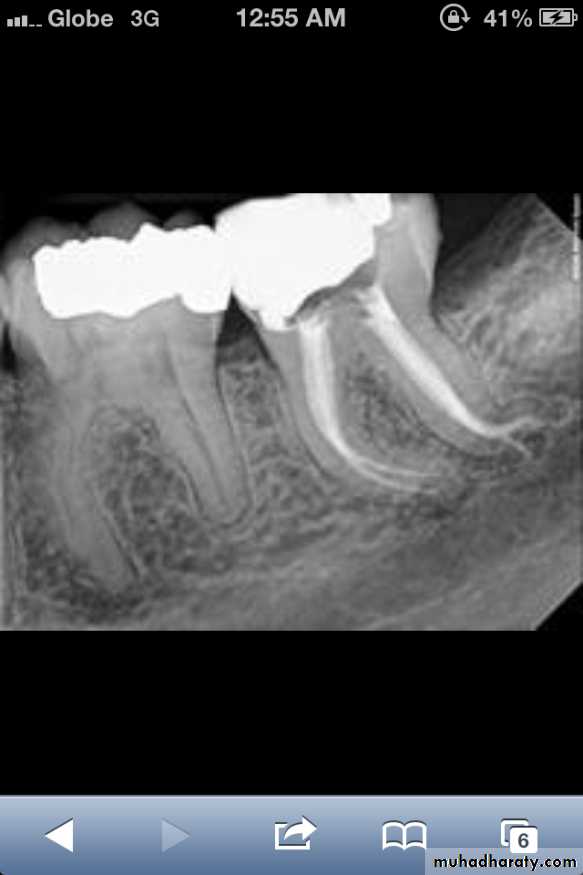

Dentin dysplasia, type I. panoramic & periapical films of the same case show the short and poorly developed roots, obliterated pulp chambers and root canals, and periapical inflammatory lesions.

Dentin dysplasia, type II. panoramic &periapical films of the same case show obliteration of the pulp chamber, reduction in the caliber of root canals, and pulp stones obscuring the flame-shaped pulp chambers.

Periapical inflammatory lesions are associated with some of the mandibular anterior teeth.